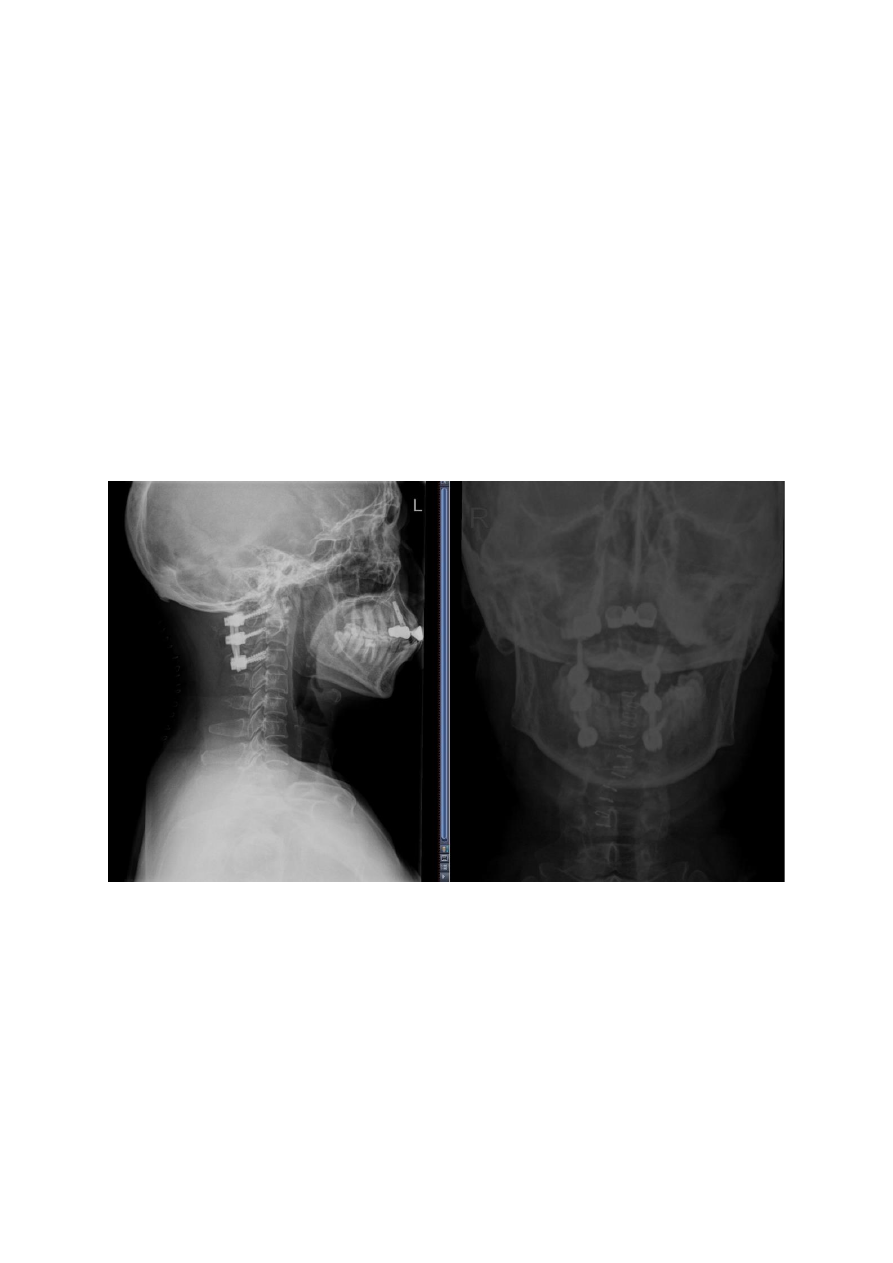

影像学检查:

1)

X

线:显示寰椎前移(图

1

)。